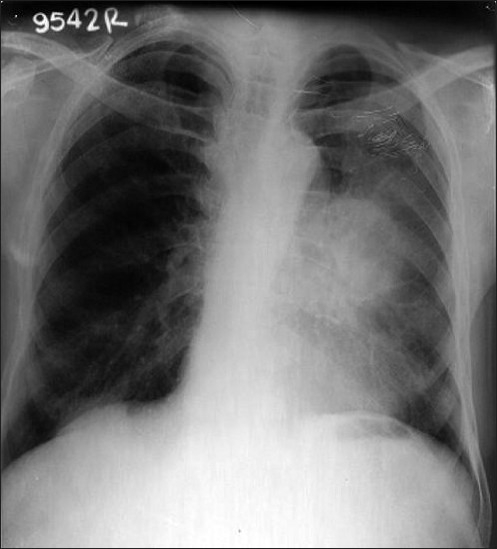

A 70-year-old man presented with a complaint of swelling and pain in the right ring finger. The swelling gradually increased in size and became painful over a one-month period. He had no other complaints. Physical examination revealed no clinical findings other than swelling in the right ring finger proximally. The swelling was of mixed consistency, tender to palpation, and it restricted finger movement. A radiograph of the right hand showed an osteolytic lesion in the proximal phalanx of the ring finger [Figure 1]. FNAC of the swelling suggested metastatic adenocarcinoma. The hematological and biochemical profiles were normal. Ultrasonography of the whole abdomen and the skeletal survey was within normal limits [Figure 2]. A plain chest radiograph showed a mass lesion in the midzone of the right lung [Figure 3]. Bronchoscopic biopsy and aspiration cytology revealed adenocarcinoma of the lung. A bone scan showed increased uptake in the proximal phalanx of the right ring finger. We planned systemic chemotherapy and palliative radiotherapy to the finger with a nonsteroidal analgesic for relieving pain.

| Figure 3 X-ray chest showing mass in left lung mid zone